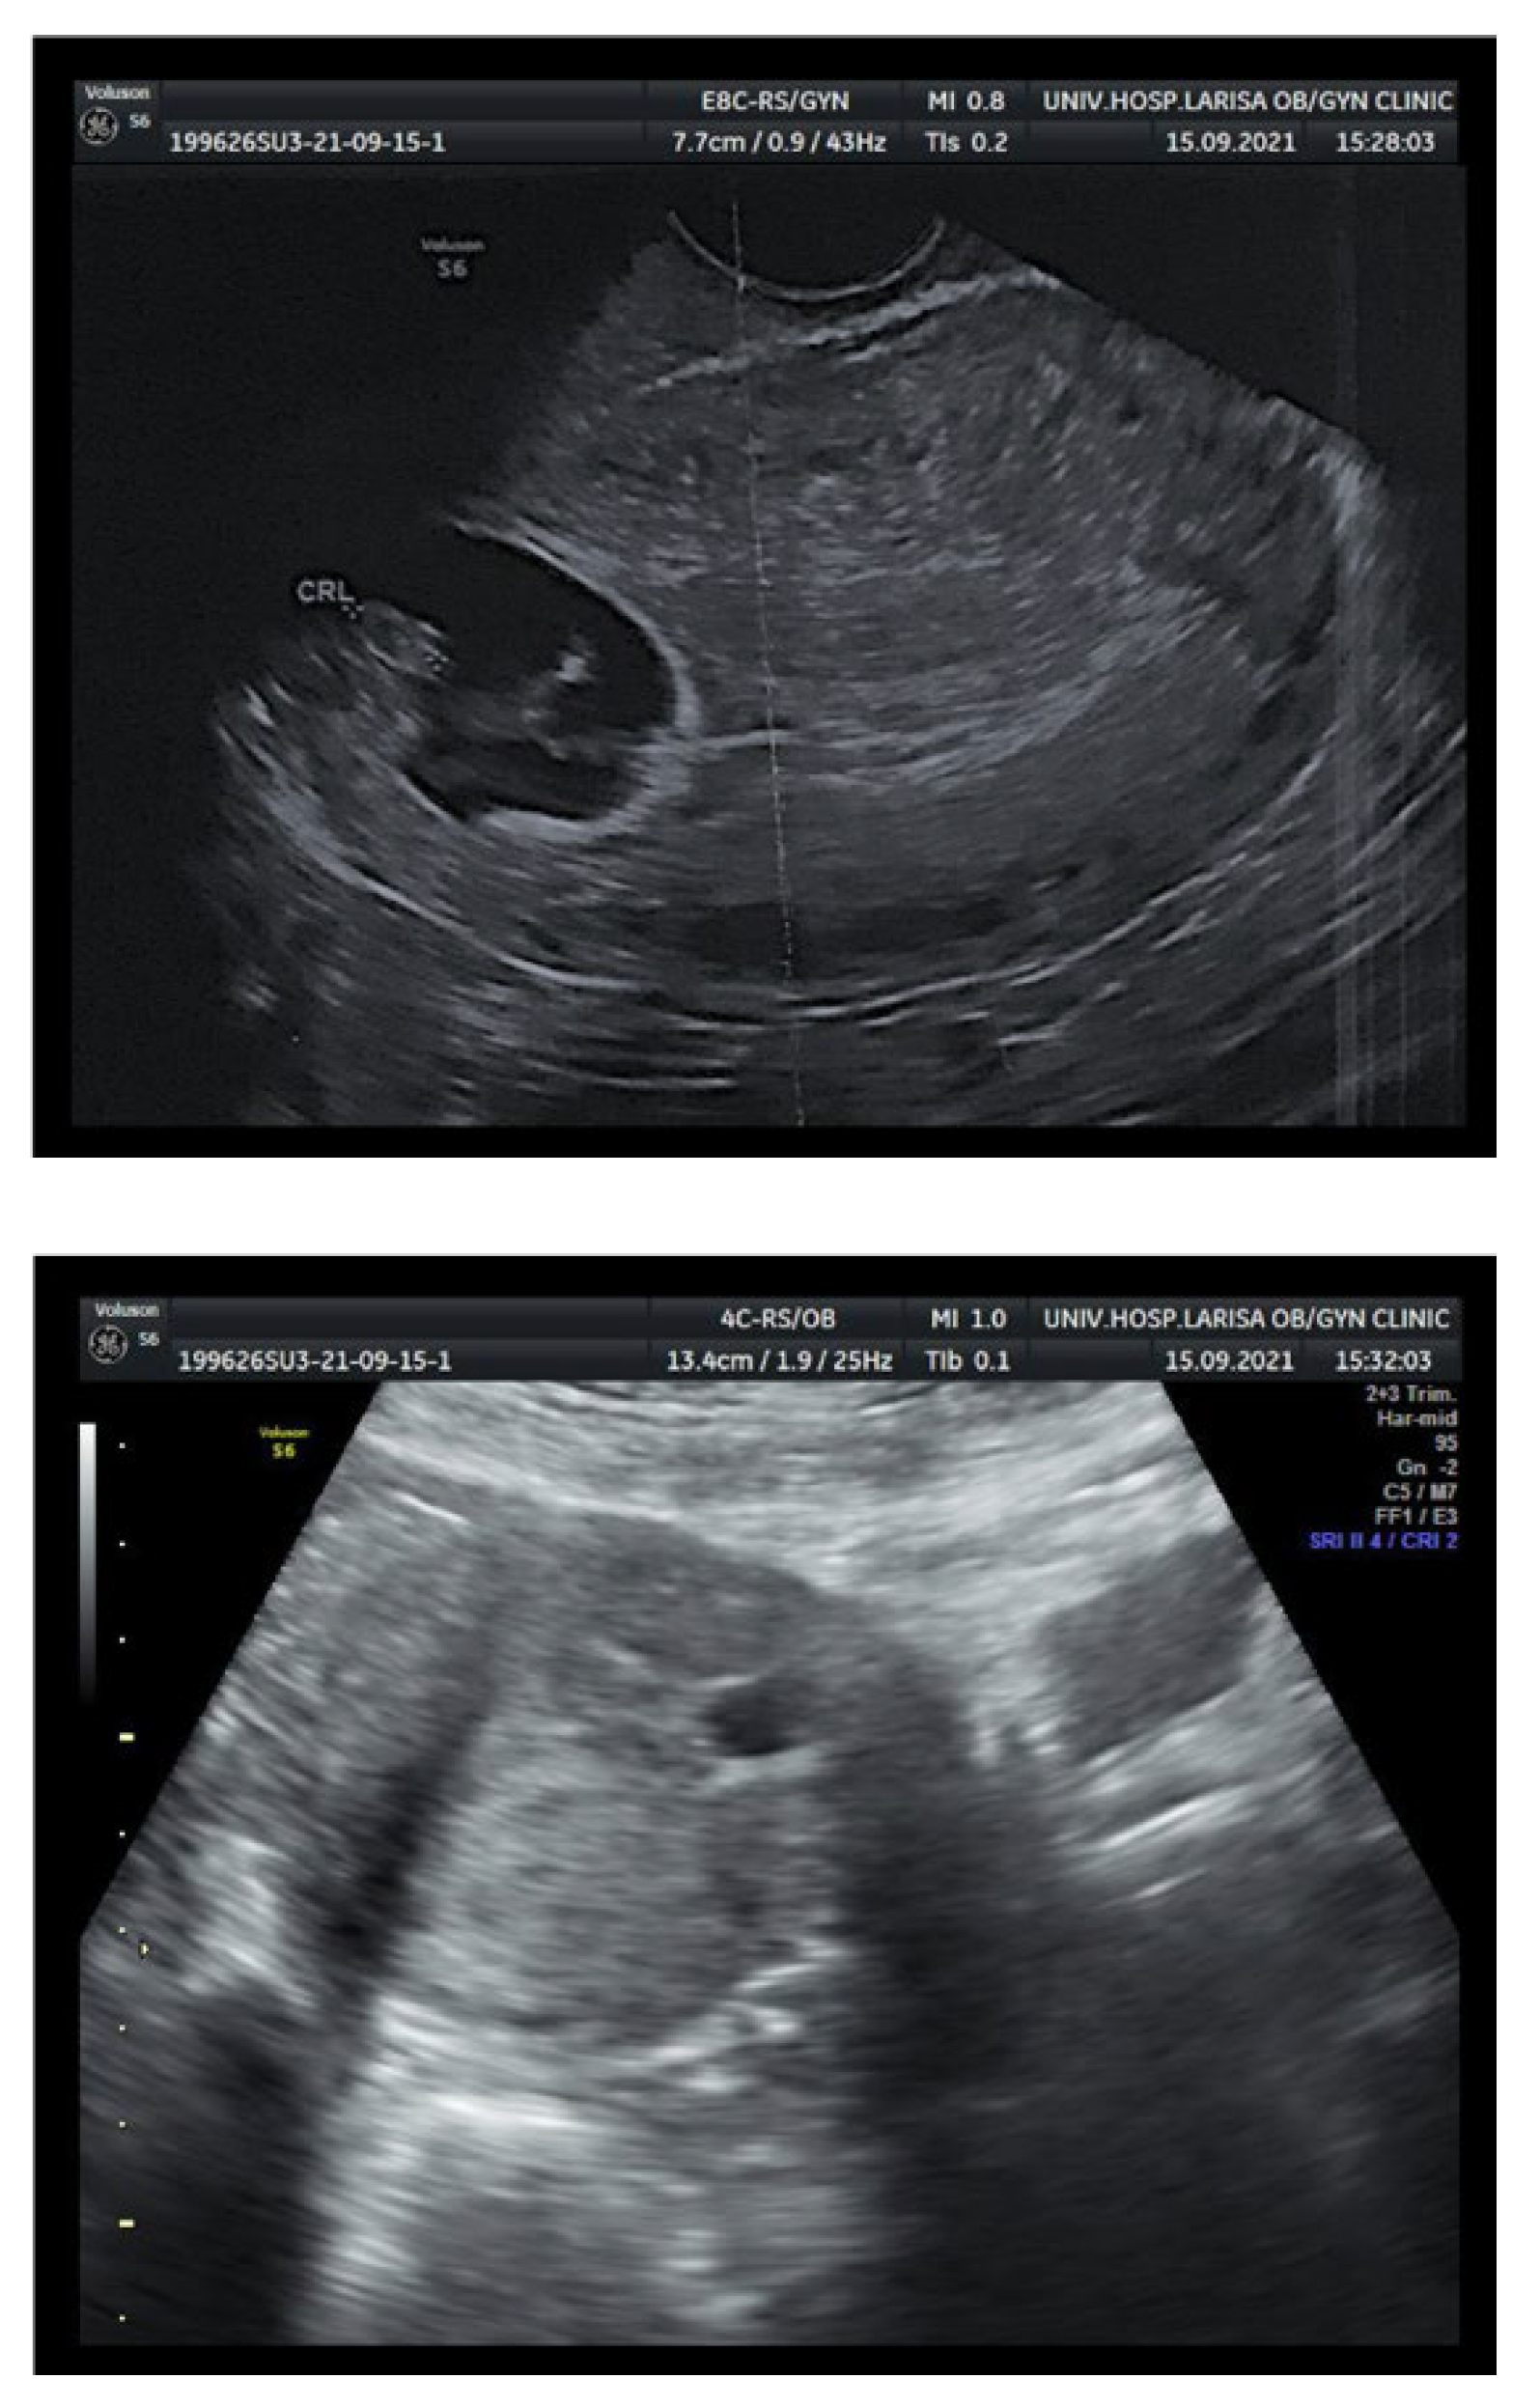

2. Case Report

| Empty endometrial and endocervical cavity |

| Nested gestational sac and placenta on/in the scar |

| Triangular (≤8/40 weeks) rounded or oval shaped gestational sac (≥8/40 weeks) filling the scar “niche” |

| Thin (1–3 mm) or absent layer of myometrium between the urinary bladder and the gestational sac |

| Distinct or rich vascular pattern around the area of the scar |

| Embryonic or fetal pole, yolk sac, or both with presence or absence of fetal cardiac activity |